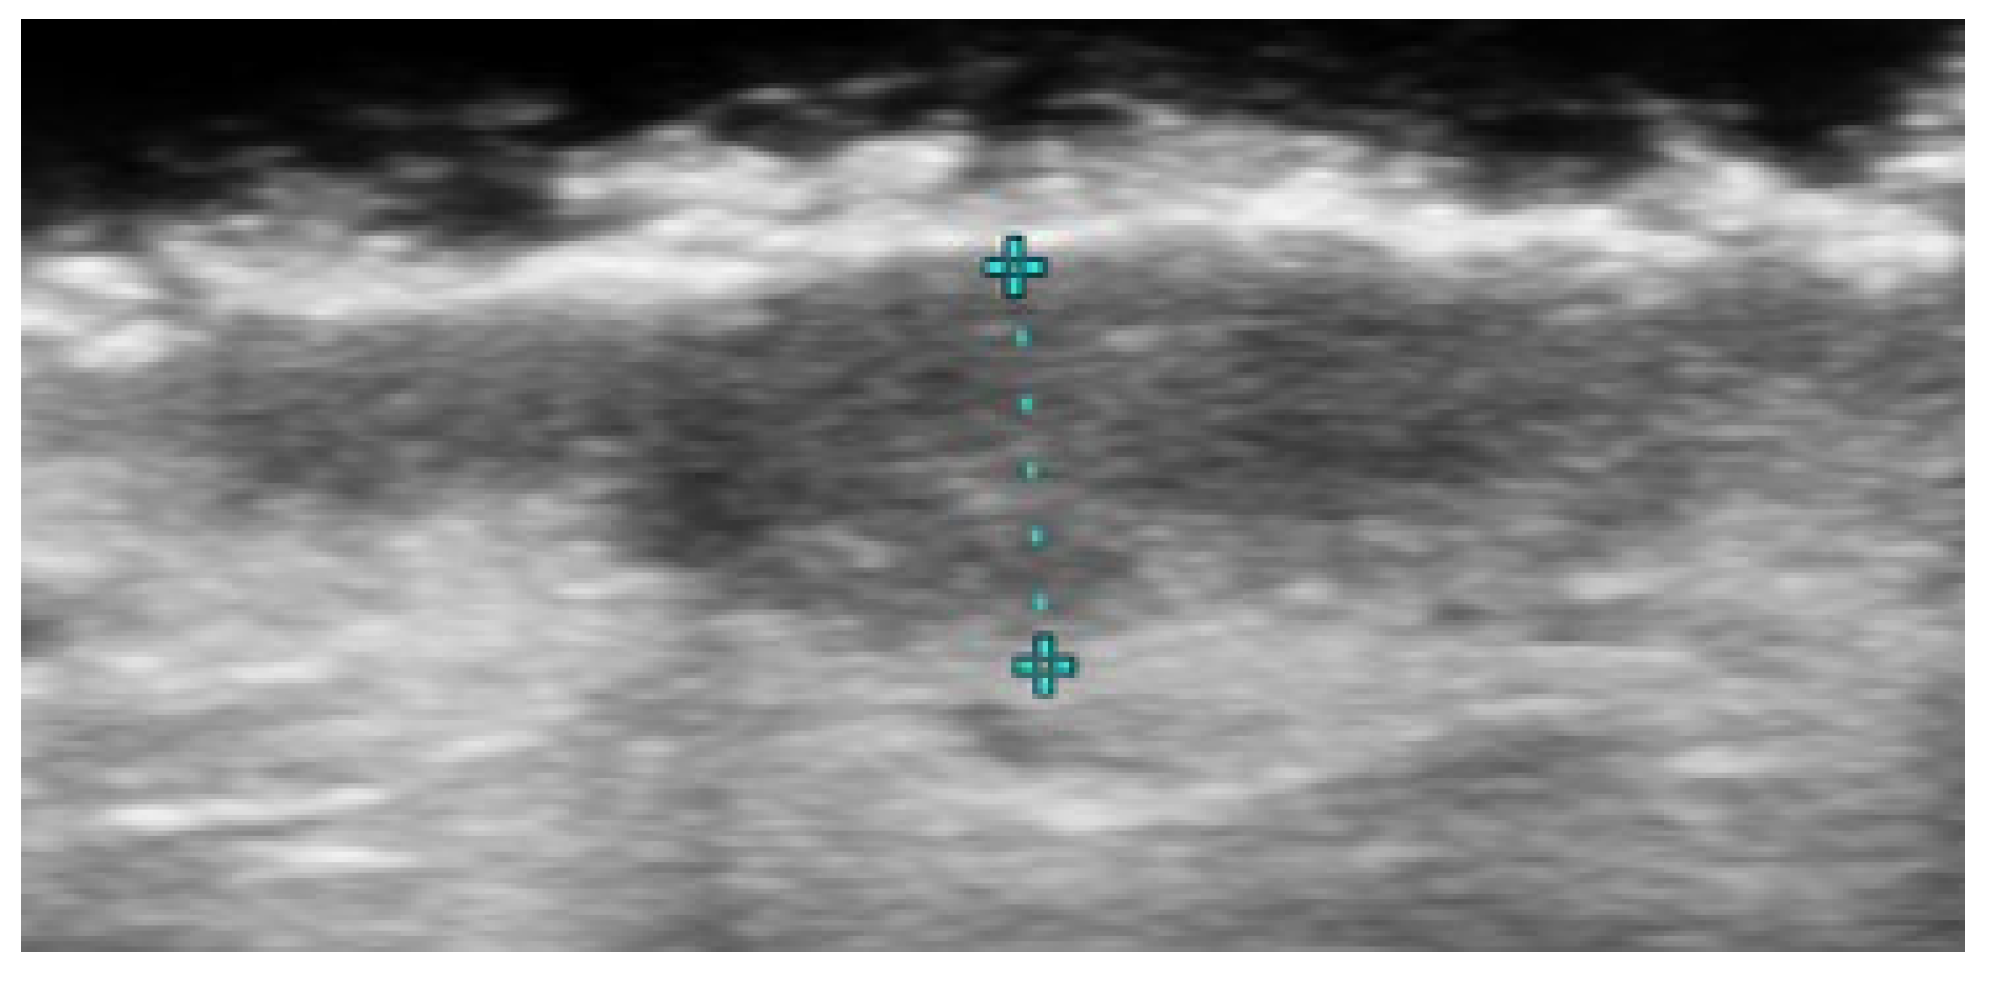

- Ranosz-Janicka, I.; Lis-Święty, A.; Skrzypek-Salamon, A.; Brzezińska-Wcisło, L. An extended high-frequency ultrasound protocol for assessing and quantifying of inflammation and fibrosis in localized scleroderma. Ski. Res. Technol. 2019, 25, 359–366. [Google Scholar] [CrossRef] [PubMed]